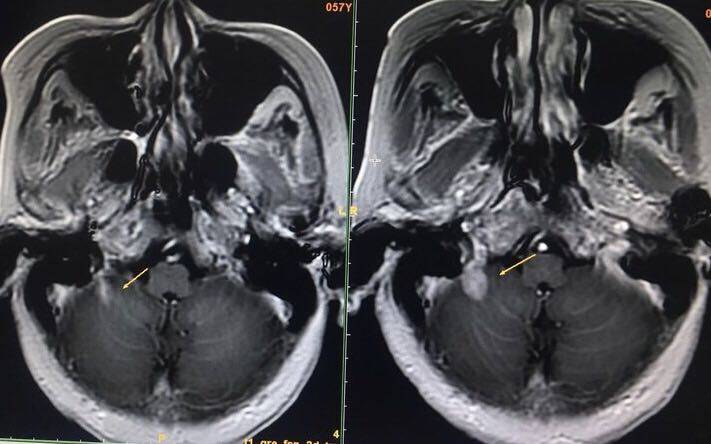

3.19 妈妈检查出来单发脑转后,3.23 吃上了第一粒2992,都说入脑不好,副作用大,我的心七上八下的,吃药一周没有反应,妈妈很高兴,可第二个星期,妈妈开始有了反应,拉肚子2-3次/天,还可以接受,可是长了一嘴的溃疡,烂舌到无法进食,十分痛苦,只能吃点粥之类,这样导致妈妈乏力,并且诸多抱怨,因为他不知自己病情,我只是告诉她这是预防性治疗,她跟我说,女儿,我本来吃中药好好的,为啥要受这个罪,要吃一个月我肯定吃不消,可是我不能告诉她,若这药有效,就要一直吃下去,她说我不想吃了啊,我连哄带骗,然后给她用了西瓜霜和康复新液漱口,于是溃疡渐渐好了,接下来又拿了两星期2992,当时我是犹豫的,想要不要给她换9291,陈波医生也这样建议过,可是我的主治医生不太同意,毕竟我们的是18突变,我又怕来回试风险太大,最终我还是决定先继续2992,一个月查了再说,今天是妈妈复查的日子,我紧张的无法工作,等妈妈一做好检查,我就去找医生看了,我那美丽善良的影像科主任尤大夫第一时间为了带来了令我激动的好消息,结节明显缩小了!太感谢了!感谢所有曾经为我提供过建议帮助的大夫!感谢菩萨保佑!我们要继续努力了!加油,妈妈!